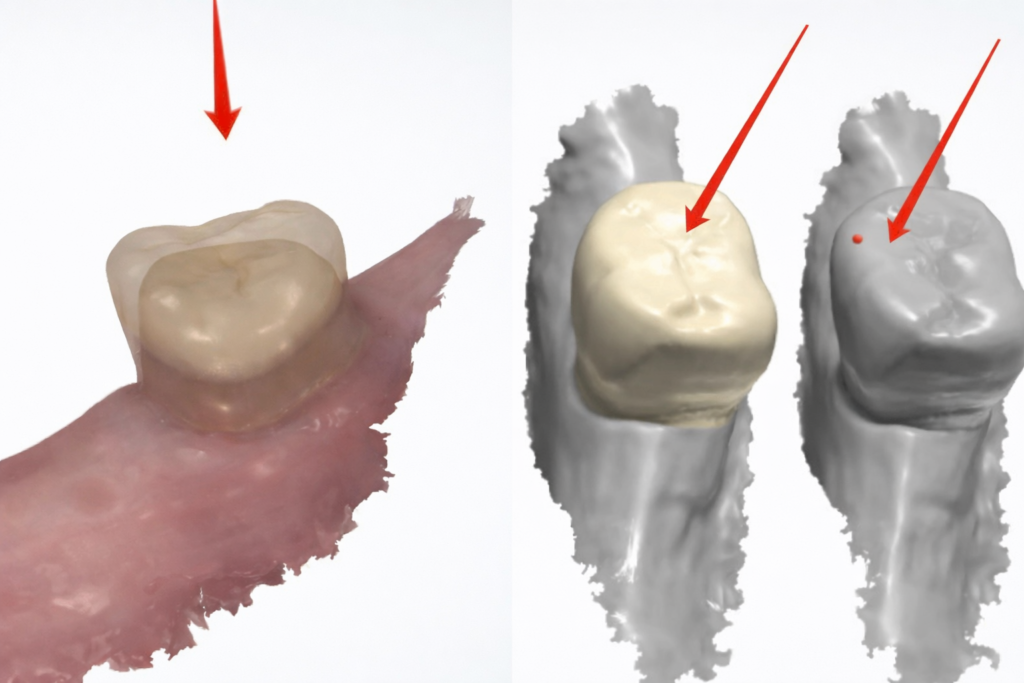

3. Easy fit to partial

On the software, we could compare the difference before and after preparation, and make a crown that would fully copy the natural tooth. In this case, the full zirconia crown could easily fit to the partial, and the dentist even would not have to make chairside adjustments.

Completely copy natural tooth